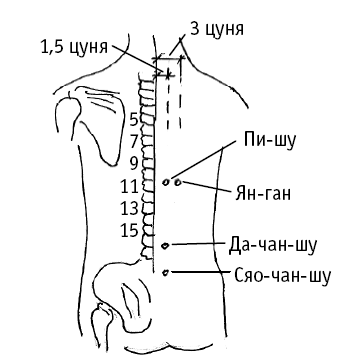

Пи-шу («точка селезенки на спине») расположена на 1,5 цуня кнаружи от места под остистым отростком 11-го грудного позвонка.

Точку используют для лечения многих проблем, вызванных плохим пищеварением (вздутие живота, боль в животе, боль в эпигастральной области, жидкий стул, снижение аппетита, похудание, а также утомляемость, бессонница).

Пи-шу также надавливают для лечения болезней, связанных с кровью (носовое кровотечение, кровохарканье, маточные кровотечения); для лечения болезни мышц и конечностей (похудание, мышечная слабость, нарушение двигательной функции конечностей).

Ян-ган («главнокомандующий внутренних органов») расположена на 3 цуня кнаружи от остистого отростка 10-го грудного позвонка.

На точку воздействуют при болезнях печени и желудка (желтуха, красно-желтый «пивной» цвет мочи, боль в печени и воспаление желчного пузыря, снижение аппетита, тошнота, рвота, вздутие живота).

Да-чан-шу («точка спины толстого кишечника») расположена на 1,5 цуня кнаружи от места под остистым отростком 4-го поясничного позвонка.

Точка применяется при заболеваниях толстого кишечника с такими симптомами: понос, запор, боль в животе, вздутие живота, урчание в животе.

Дополнительный эффект от воздействия: восстановление нормального мочеиспускания; лечение боли и напряжения в пояснице и бедре.

Сяо-чан-шу («точка спины тонкого кишечника») расположена на 1,5 цуня кнаружи от места под остистым отростком 6-го поясничного позвонка.

Точка применяется при заболеваниях тонкого кишечника с такими симптомами: снижение аппетита, урчание в животе, запор, понос.

Акупрессура точки также используется при недержании мочи или затрудненном мочеиспускании; при поллюциях, маточных кровотечениях; при болях в пояснице и бедре, напряжении мышц позвоночника; при геморрое.

Пи-шу («точка селезенки на спине») расположена на 1,5 цуня кнаружи от места под остистым отростком 11-го грудного позвонка.

Точку используют для лечения многих проблем, вызванных плохим пищеварением (вздутие живота, боль в животе, боль в эпигастральной области, жидкий стул, снижение аппетита, похудание, а также утомляемость, бессонница).

Пи-шу также надавливают для лечения болезней, связанных с кровью (носовое кровотечение, кровохарканье, маточные кровотечения); для лечения болезни мышц и конечностей (похудание, мышечная слабость, нарушение двигательной функции конечностей).

Ян-ган («главнокомандующий внутренних органов») расположена на 3 цуня кнаружи от остистого отростка 10-го грудного позвонка.

На точку воздействуют при болезнях печени и желудка (желтуха, красно-желтый «пивной» цвет мочи, боль в печени и воспаление желчного пузыря, снижение аппетита, тошнота, рвота, вздутие живота).

Да-чан-шу («точка спины толстого кишечника») расположена на 1,5 цуня кнаружи от места под остистым отростком 4-го поясничного позвонка.

Точка применяется при заболеваниях толстого кишечника с такими симптомами: понос, запор, боль в животе, вздутие живота, урчание в животе.

Дополнительный эффект от воздействия: восстановление нормального мочеиспускания; лечение боли и напряжения в пояснице и бедре.

Сяо-чан-шу («точка спины тонкого кишечника») расположена на 1,5 цуня кнаружи от места под остистым отростком 6-го поясничного позвонка.

Точка применяется при заболеваниях тонкого кишечника с такими симптомами: снижение аппетита, урчание в животе, запор, понос.

Акупрессура точки также используется при недержании мочи или затрудненном мочеиспускании; при поллюциях, маточных кровотечениях; при болях в пояснице и бедре, напряжении мышц позвоночника; при геморрое.